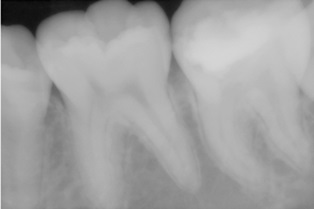

H23年6月に来られたのでその後どうなっているか心配なので経過観察をしたいのでH23年9月中旬頃にリコールの電話したが忙しくて来れないとの事。その時も電話ですが特に疼痛等の自覚症状はなしとの事でした。H23年12月にやっと来院して頂く事ができたので取り合えず経過観察させてもらいました。

所見的にはもちろん何もしなくても痛いようなことはなく、噛んだ時の痛みもなし、神経の反応もありましたレントゲンで確認するとドックベストセメントを置いた部分の下に新しい歯質ができ始めているように見えます。もう6カ月ほど待って最終処置をしていきたいと思います。